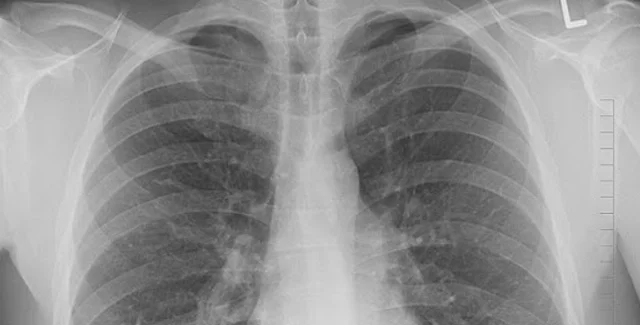

За неделю количество пневмоний увеличилось в 5 раз по сравнению с недельной заболеваемостью в июле. Об этом сообщил глава Минздрава Максим Степанов на брифинге.

"Существенно увеличилось количество людей с пневмониями, за прошедшую неделю это 22 400 человек. Для понимания, например, в неделю с 13 по 19 июля всего было пневмоний 4 424, то есть более чем в 5 раз рост ", – сказал Степанов.

По его словам, сейчас растет не только количество заболевших, но и количество госпитализаций.